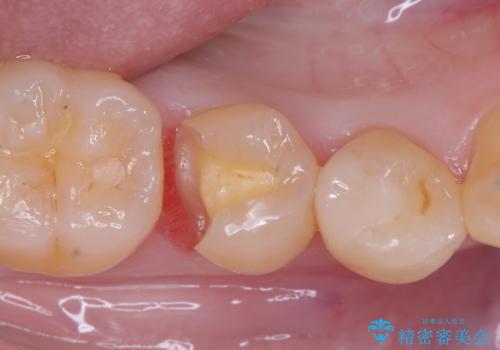

セラミックインレーによる虫歯治療

- 右下5の虫歯をセラミックインレーで修復しました。虫歯は進行することで歯に悪影響を及ぼし、放置するとさらなる問題を引き起こす可能性があります。再発のリスクをできるだけ回避するため、セラミックインレーを用いて治療を行いました。

装着する際にはラバーダムを使用しています。